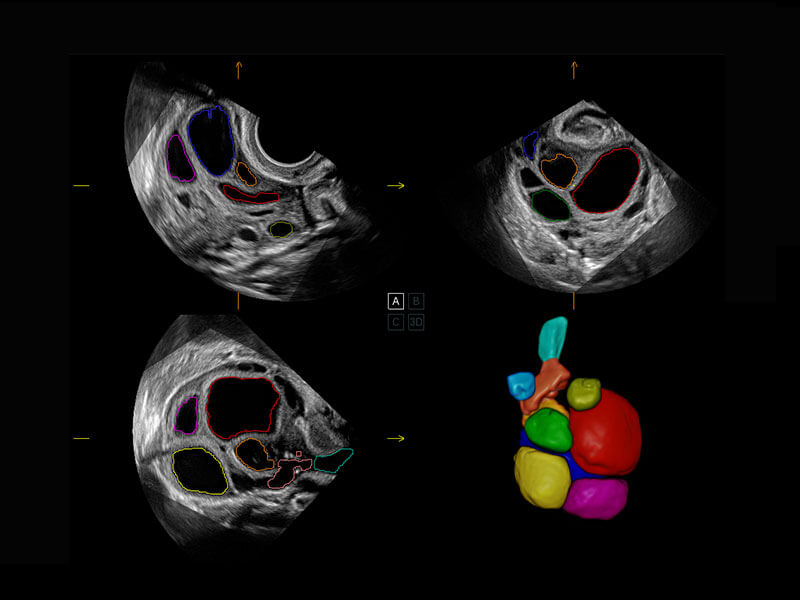

新生兒脊髓圓錐

新生兒心臟